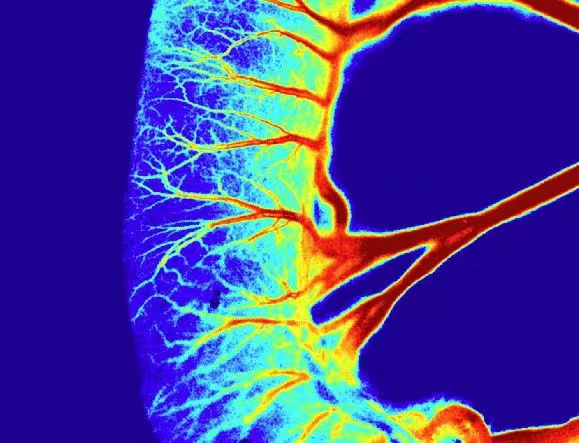

股动脉血流监测

下肢局部血流监测成像